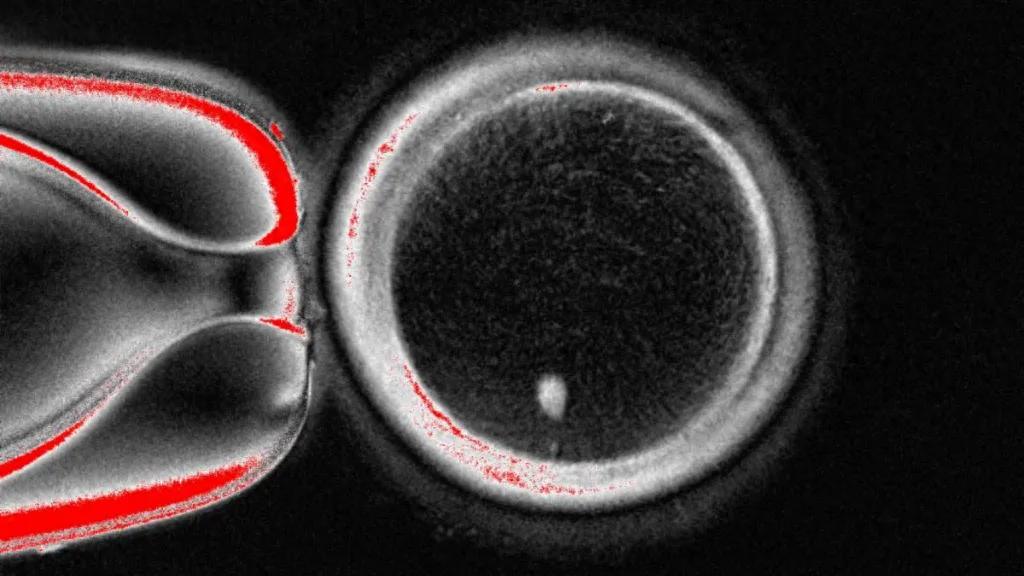

The egg observed under a microscope contains genetic material extracted from skin cells (Oregon Health & Science University website)

The research team extracted the nucleus from skin somatic cells and implanted it into an enucleated donor egg.

To solve the problem of the extra chromosomes, the researchers induced a process called "mitochondrial meiosis," which simulates natural cell division, leading to the discard of one set of chromosomes, leaving behind a functional gamete.

The researchers fertilized 82 functional eggs in the laboratory, and only 9% developed to the blastocyst stage within six days, at which point the experiment was stopped, coinciding with the time when embryos are typically transferred to the uterus in in vitro fertilization treatment.